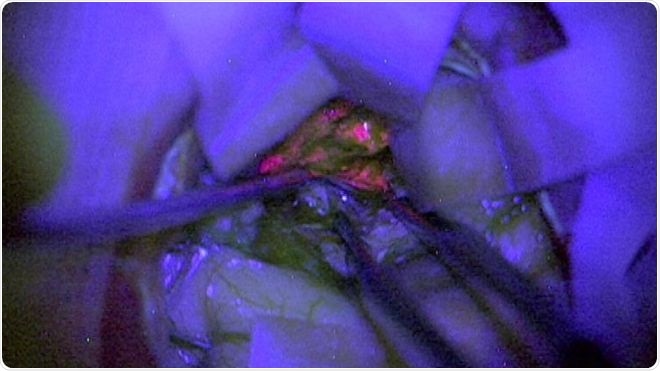

According to the scientists the brain tumours called gliomas are specific. When patients with them consume a drink containing 5-aminolevulinic acid or 5-ALA, it accumulates in the tumour. 5-ALA is known to accumulate in cancer cells that are fast growing. The reason behind this is the fact that the tumours do not contain an enzyme that is necessary to break down the chemical. This chemical contained a pink colour that appeared in the tumours that are most aggressively growing. While operating the surgeon would be able to clearly visualize the tumour tissues and differentiate it from the healthy brain tissues, they add. This can make the operation easier and safer.

When operating the surgeons looked at the fluorescent tissues of the brain that contained the tumour tissues. In 85 patients they were clearly able to see the tumour tissues as glowing pink. Among these 81 were actually high grade gliomas as confirmed from pathological specimens removed from the brain. One of the glowing tumours was found to be actually low grade tumour. Among the 14 patients in whom there was no glow of the tumours, seven were found to be low grade and seven tumours could not be assessed for their severity.